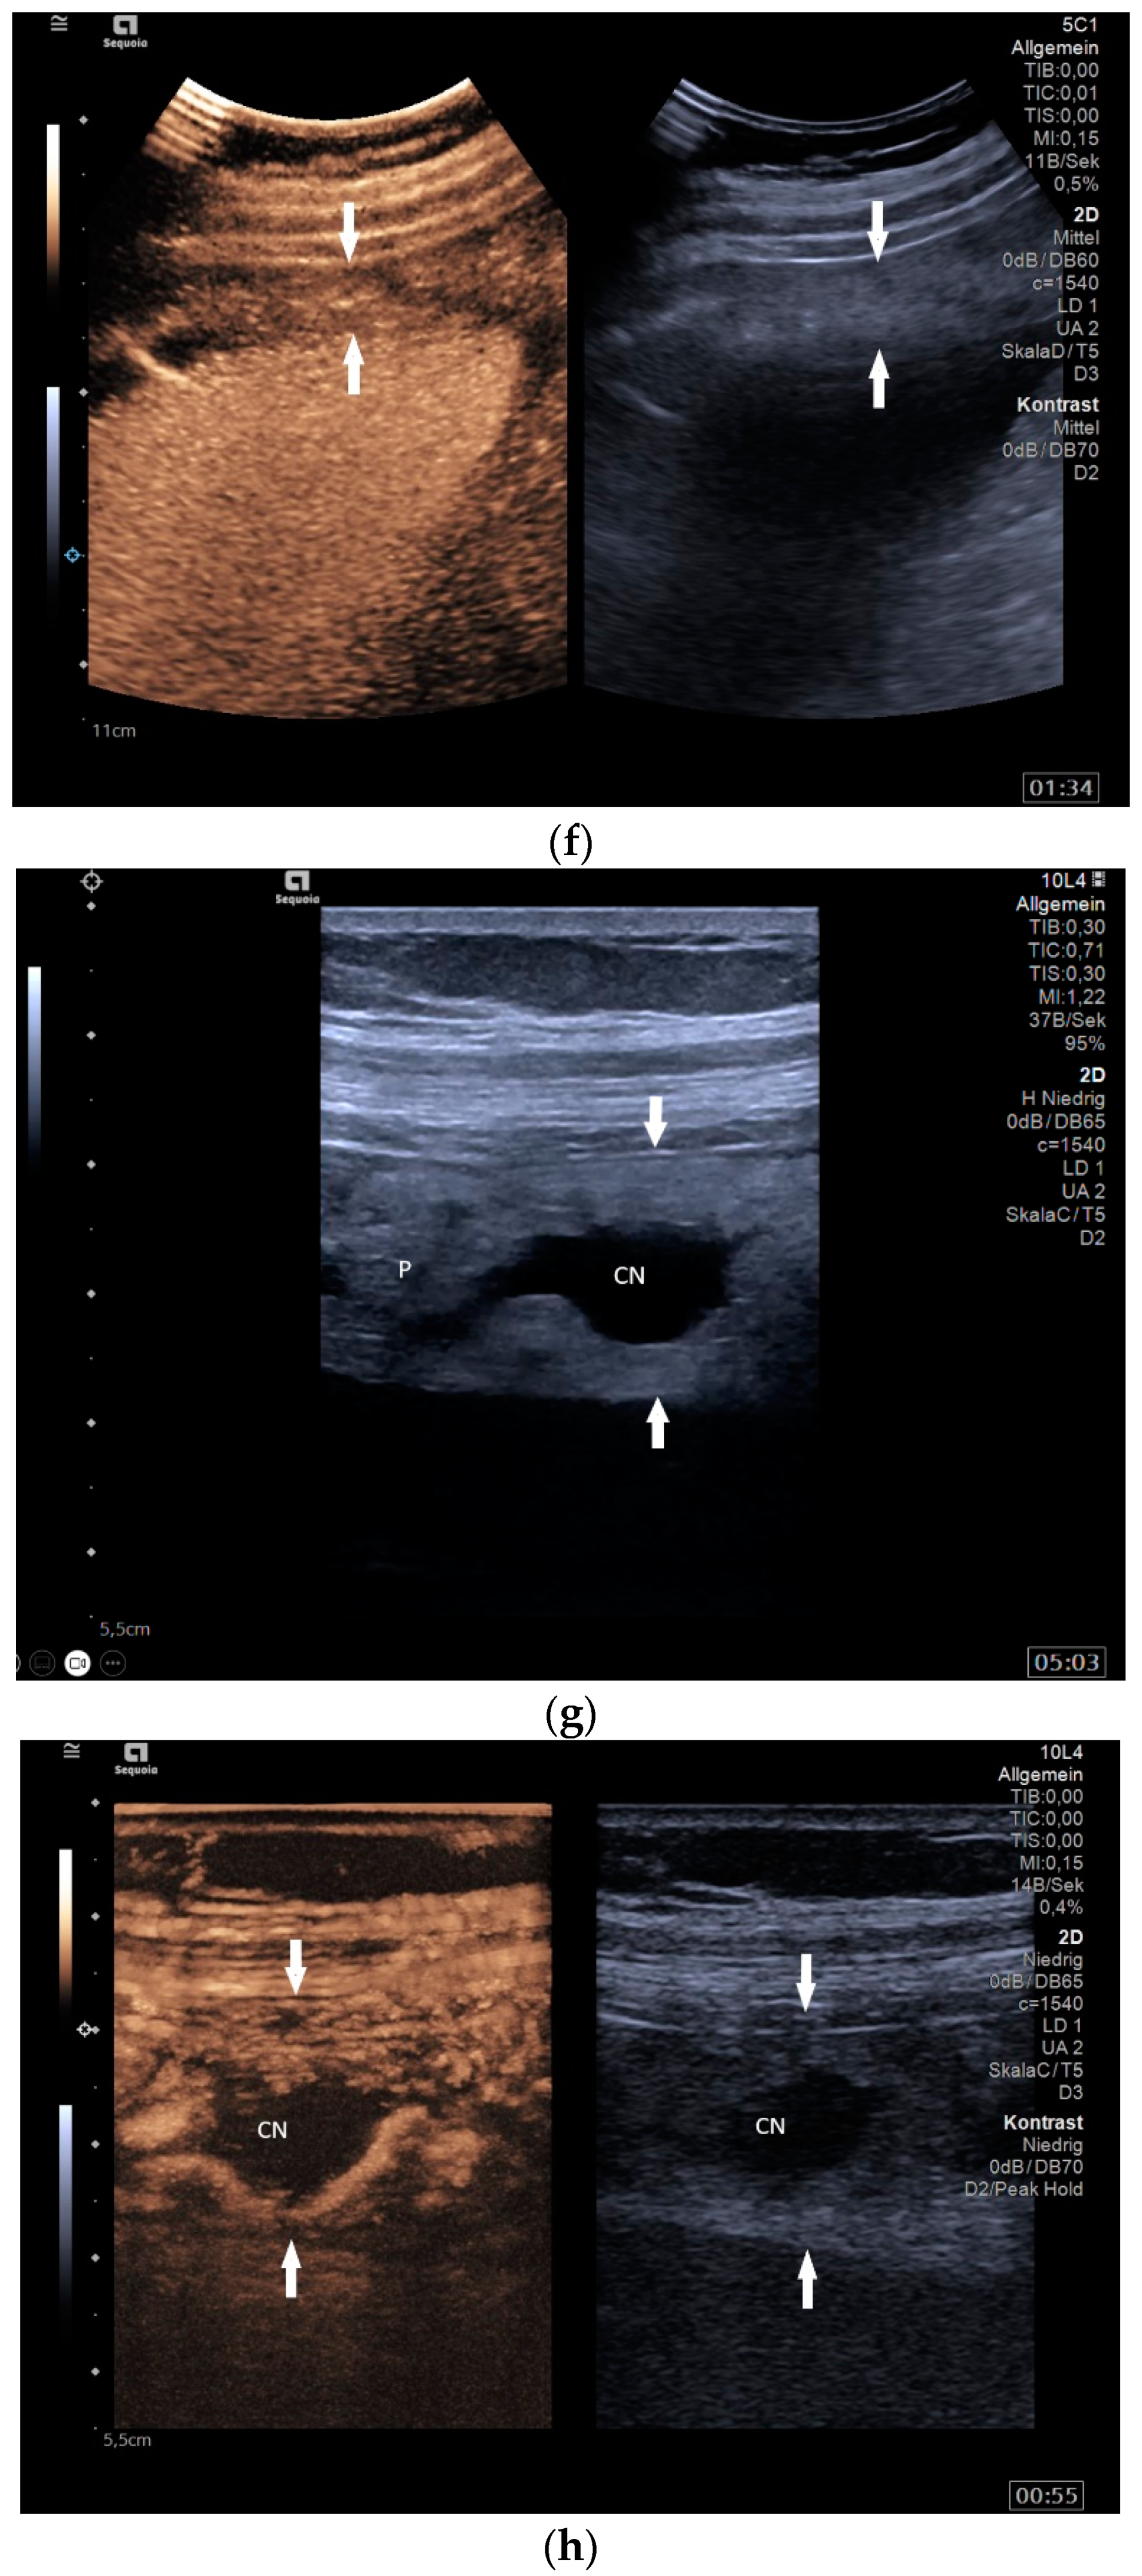

Mediastinal lymph nodes can be biopsied using EUS- or EBUS-guided FNA or FNB. Via paraoesophageal, paragastric, and paraduodenal access, histological specimens can be obtained from further lymph nodes using EUS-guided sampling [41,43,45,46,47,48,49,50] [Figure 2a–m]. The most important differential diagnoses are metastases of malignant tumors, non-Hodgkin’s and Hodgkin’s disease and other infections.

Figure 2.

A case of extrapulmonary tuberculosis: 33 y/o male from a country at high risk of tuberculosis. Thoracic pain and fever led to a suspicion of pericarditis. There was no pericardial effusion. There were no pulmonary infiltrations or pleural effusions in the chest CT, but there were enlarged mediastinal lymph nodes. Ultrasound and CT also showed subdiaphragmal enlarged lymph nodes and small nodular splenic changes. The diagnosis was confirmed using the transgastric EUS-guided biopsy (19 G Olympus) of the lymph nodes in the hepatic hilum. Enlarged lymph nodes in the hepatic hilum (a); adjacent to the pancreatic head (b); transabdominal ultrasound (TUS) using a linear transducer of 9 MHz. The hypoechoic central parts are conspicuous (a,b). Rounded lymph nodes are observed as being peripancreatic (c) and as being in close proximity to the gallbladder wall (d). The lymph nodes are visualized between the markers. In the EUS, paragastric lymph nodes are enlarged, rounded, very hypoechoic, with hypoechoic central parts, and forming conglomerates. A central vascular hilum cannot be delineated in the CDI (e). The hypoechoic central parts are softer during elastography (f). EUS also shows enlarged hypoechoic lymph nodes in the hepatic hilus, with hypoechoic central parts that lack a central vascular hilum (g). Elastographically, the lymph nodes are indifferent (h). The diagnosis is confirmed using EUS-guided biopsy (i) with evidence of granulomatous inflammation, caseous necrosis, detection of acid-fast rods, and Mycobacterium tuberculosis in the PCR. In the spleen, single hypoechoic lesions < 5 mm are visible during transabdominal ultrasound using a linear transducer of 9 MHz. Otherwise, fine-grained hypoechoic lesions can only be guessed at (j). With magnification using a 9 MHz transducer, multiple hypoechoic lesions < 3 mm can be delineated (k). These do not reveal any vessels in the Power Doppler (l). EUS confirms multiple hypoechoic splenic lesions, in line with splenic tuberculosis (m).